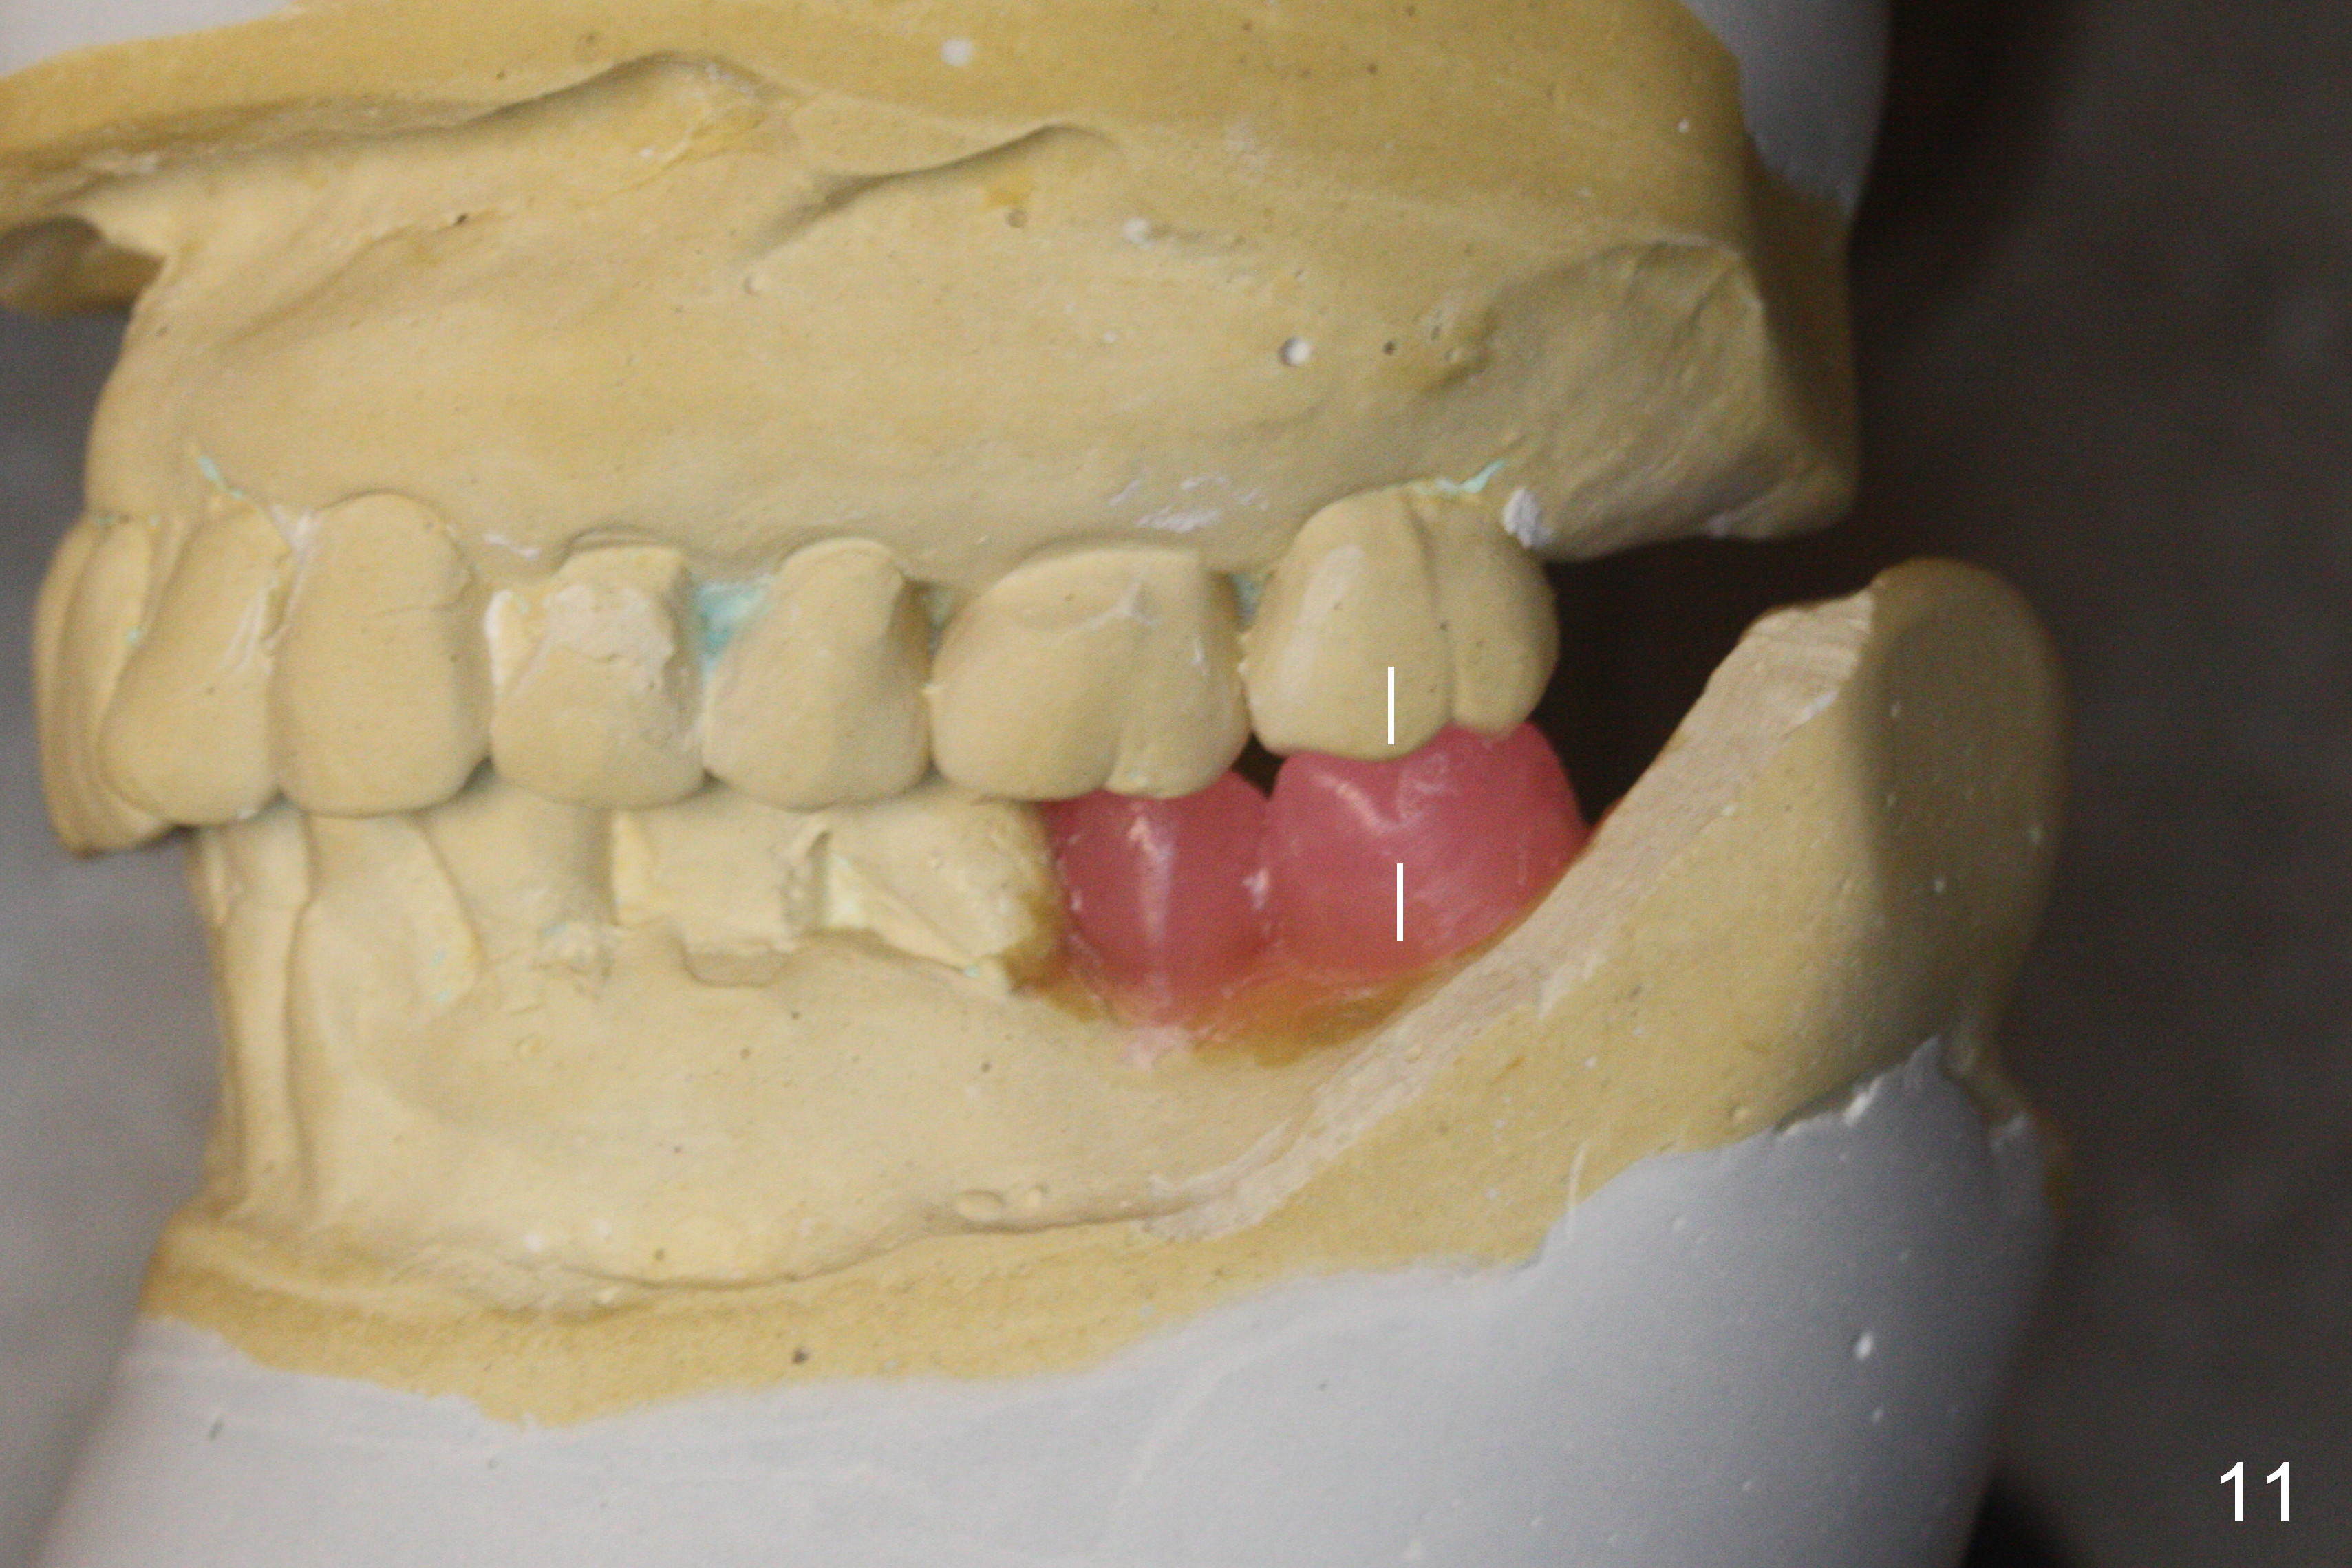

A new setup of wax up is established immediately preop (Fig.10) to have atypical Class I occlusion between the upper 2nd molar and the lower 1st one (Fig.11 straight lines). Take photos of the occlusion post cementation.